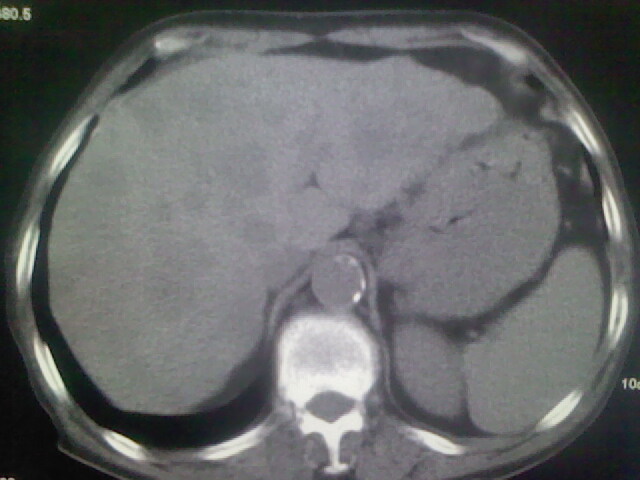

男,70y,胃占位,重度贫血,黑便3月余,伴恶心,纳差,乏力

肝内弥漫低密度---转移瘤

右上肺周围型肺癌,肝内多发低密度影---转移瘤?建议增强;胃壁明显增厚.

1)考虑右肺上叶周围型肺癌并纵隔及右颈部淋巴结转移,肝脏多发性转移。2)肺气肿。3)冠状动脉及主动脉钙化。

支持右肺上叶周围型肺癌伴肝内多发转移.胃建议充盈后重扫描.慢性支气管炎伴肺气肿.